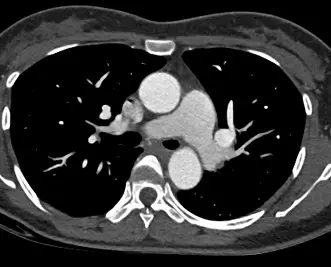

39歲女性,健康檢查時發現有心雜音,進一步做了電腦斷層檢查影像如附圖,最可能的診斷為下列何者?

本題核心在於胸部電腦斷層(CT)影像中,辨識主動脈與肺動脈間的異常交通(ductus arteriosus),與其他主動脈病變(pseudoaneurysm、aneurysm、coarctation)的影像表徵進行鑑別。

– 第二張圖在稍高一平面,可見該異常血管在主動脈弓下方走行,與左鎖骨下動脈、左肺動脈走行相近,但仍維持獨立連通通道。